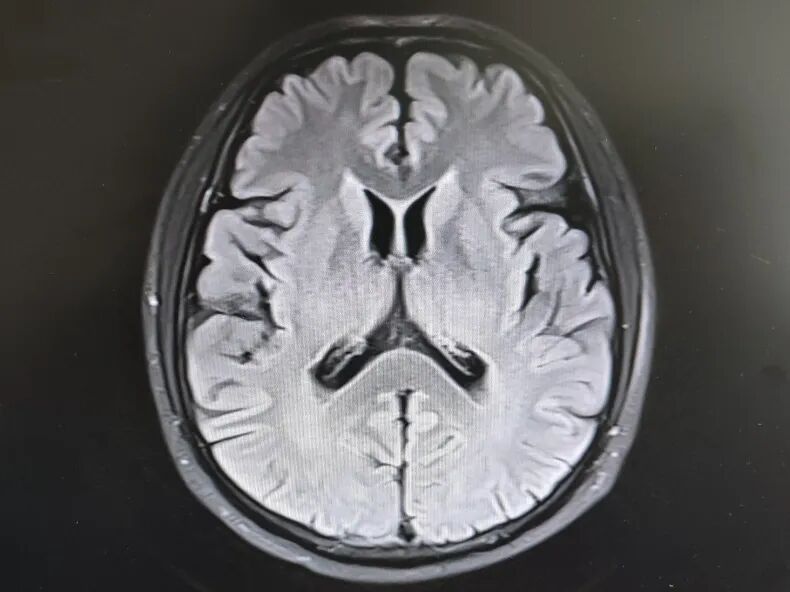

引言 生活中,很多人会突然出现“看东西重影”的情况,往往以为是眼睛疲劳或近视加深,并没有太当回事。然而,这背后可能隐藏着甲亢、脑梗、重症肌无力甚至肿瘤等十余种疾病的信号,是一个需要警惕的“隐形杀手”。 面对这类病因错综复杂的“复视”患者,市二院神经内二科赵智江主任带领团队,凭借丰富的临床经验和深厚的神经疾病诊疗功底,抽丝剥茧,多次成功揪出导致视物成双的“真凶”,为患者赢得了宝贵的治疗时机。 Part.01 复视背后,病因五花八门 神经内二科团队诊治了多位以“视物成双”为主诉的患者,其最终病因各异,充分体现了神经科疾病“同症异源”的复杂性。 以为是眼病,其实是甲亢 患者因复视就诊,经查双眼突出,影像检查发现控制眼球的肌肉异常肥厚。结合甲状腺功能检查,最终确诊为“甲亢性眼肌病”,其原因在甲状腺功能亢进的眼部表现。后经针对性纠正甲状腺功能,患者复视症状显著改善,眼外肌肥厚得到有效控制。 眼眶核磁 甲功结果 眼球状态 复视眼痛,原是痛性眼肌麻痹 患者右眼不仅看东西重影,还出现上睑下垂、眼痛等症状。团队排除其他可能后,诊断为痛性眼肌麻痹(Toloas-Hunt综合征),这是一种自身免疫性炎症。经治疗,患者眼睑下垂症状减轻,眼痛及复视基本消失,眼球运动范围显著恢复。 梅毒隐匿,损伤颅神经 患者因眼皮抬不起、眼球转动不灵并视物重影入院。常规血清检查发现梅毒抗体阳性,排除其它原因导致的复视,最终明确为“神经梅毒”侵蚀颅神经所致。确诊后立即给予驱梅治疗,效果明显,眼皮能抬起来了,重影消失了,眼球转动也灵活了。 糖尿病悄悄损伤神经 两位糖尿病患者,均以突发复视就诊。团队精准判断,发现分别是高血糖损伤了“动眼神经”和“外展神经”,属于糖尿病性单神经病变,表现为不同类型的复影(上下重影或水平重影)。明确诊断后,经严格控糖,辅以营养神经药物等综合对症治疗,患者病情好转,顺利出院。 脑梗“瞄准”不同区域 三位患者均因复视就诊,但伴随症状各异,有的行走不稳,有的走路右偏。赵智江主任团队通过精细的神经系统查体,精准定位于中脑的动眼神经核、桥脑的内侧纵束等。不同脑区梗死,复视的表现也完全不同。后通过溶栓药物、抗血小板药物、改善循环治疗等针对性治疗,辅以康复治疗,患者身体逐渐好转,出院时已无视物成双症状。 三位患者的核磁 典型信号——晨轻暮重 患者出现复视,伴言语不利、吞咽困难、饮水呛咳等症状。其中复视有个鲜明特点——早晨轻、傍晚重,疲劳后加重。经专项检查,确诊为“重症肌无力”(眼肌型)。这是一种神经肌肉接头疾病,免疫调节治疗可有效控制。经过一段时间的治疗,患者复视症状明显缓解,言语不清、吞咽困难症状得到显著改善。治疗前患者只能进食流食,治疗后可自主进食固体食物。 肿瘤病史者,需警惕转移 淋巴瘤患者在化疗期间出现复视和面瘫。团队通过脑脊液等深入检查,排除感染等因素,最终诊断为脑膜癌病。 嗜睡头晕,病因在营养 患者急性起病,表现为复视、头晕、嗜睡、走路不稳。团队结合其既往史和典型眼球活动障碍,迅速锁定病因——因维生素B1严重缺乏导致的“韦尼克脑病(Wernicke)”。补充维生素B1一周以后,患者复视症状改善、走路平稳、神志清楚,可独立行走。 Part.02 精准诊疗,揪出“元凶”是关键 赵智江主任指出:“复视只是一个临床症状,其背后可能是内分泌、炎症、代谢、脑血管、自身免疫、肿瘤等多种病因在神经系统上的投射,涉及学科广泛。” 市二院神经内二科团队通过详细追溯病史、进行一丝不苟的神经系统专科查体(尤其是眼球运动检查),初步判断病变可能位于动眼、滑车、外展神经的神经核团,神经及其所支配的肌肉、神经-肌肉接头等部位,然后精准选择并解读影像学、免疫学、生化及脑脊液等检查结果,最终整合信息,明确诊断,为患者制定出针对性的治疗方案。 市二院神经内二科在赵智江主任的带领下,始终致力于复杂疑难神经系统疾病的诊疗攻坚。科室凭借严谨的临床路径、对神经解剖与病理生理机制的深刻把握,以及精湛的诊疗技术,为众多罕见病与危重患者精准定位病因、制定个体化治疗方案,有效提升了救治成功率与患者长期生活质量。 提醒市民:如果突然出现视物重影,尤其是伴有眼皮下垂、眼球转动不灵、疼痛、头晕、行走不稳或其他神经系统症状时,切勿掉以轻心,应及时重视,这些症状有时可能与神经系统疾病相关。为了明确原因,获得更全面的评估,您可以考虑到神经内二科就诊,由专业医生进一步检查与诊断,以便尽早获得适合的照顾与治疗。 Part.03 人民医院 人民名医 赵智江 主任医师 副教授 ·葫芦岛市第二人民医院神经内二科主任 ·中国卒中学会高级会员 ·中国老年保健医学研究会老年脑血管病分会委员 ·北京神经内科学会脑小血管病学会委员 ·安徽医药杂志审稿专家 ·辽西神经疾病专科联盟理事 ·辽西认知功能障碍联盟理事 ·辽西神经免疫学会委员 ·葫芦岛市医学会神经病学分会委员 专业特色:以脑血管病为核心研究方向,擅长各类神经系统疾病的诊疗,尤其在脑血管病、帕金森综合征、头晕、头痛、癫痫、重症肌无力、多发性硬化等神经免疫性疾病以及其它神经系统疑难、危重疾病的诊疗方面积累了丰富的临床经验。 出诊时间:每周一、周四全天 咨询热线:0429-8010317